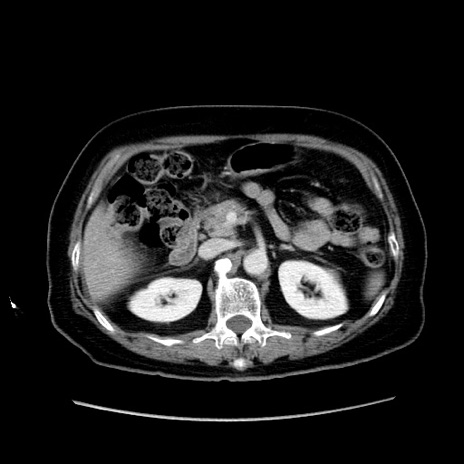

症例19(横断像)

冠状断像

【症例】80歳代女性

【主訴】下腹部痛

【現病歴】約8時間前より下腹部痛の出現あり、救急外来受診。

【既往歴】両側付属器切除

【身体所見】意識清明、下腹部正中に手術痕あり、その部位に一致して圧痛と反跳痛あり。腸蠕動音は亢進。

【データ】WBC 9300、CRP 0.15